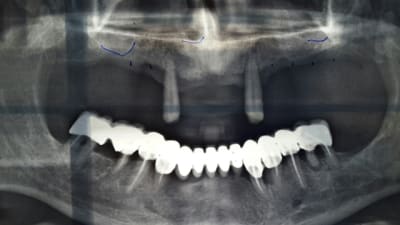

voila desolée pourla qualité des photos. j'ai pas pris encore en bouche mais il ne découvre pas du tout. le guide radio a été fait à partie de son stellite. les reconstructions panoramique du scan sont un peu bizarre mais sur les coronales je pense m'en sortir avec les longueur que j'ai dit.

Pano lkdjko - Eugenol

Je vois au moins 5 racines "infectées" et je suis gentil.

Les "germes paro" présents partout ne sont pas top pour l'implanto du haut.

Pour le budget, le patient (et toi) a les moyens de perdre des implants en haut ?